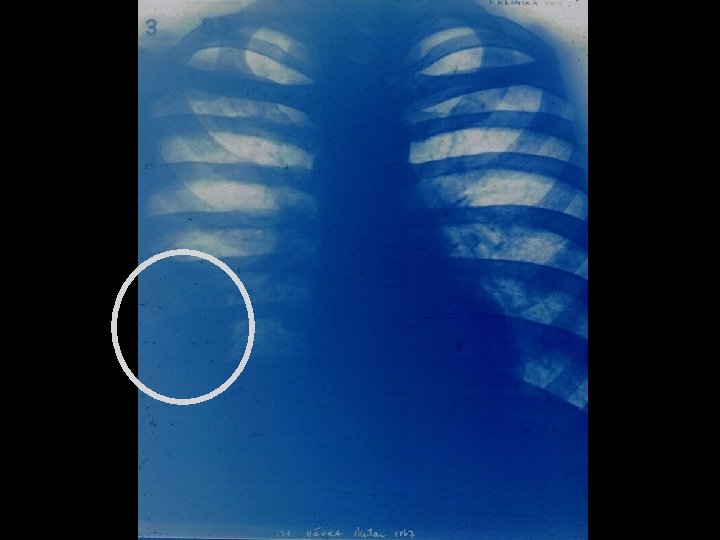

Vaskulitické syndromy 3 § Wegenerova granulomatoza nekrotizující vaskulitida s tvorbou granulomů • sinusitis • plicní infiltráty • nefritis • biopsie ledviny nebo nosní sliznice • C-ANCA, PR-ANCA • GN s tvorbou srpků • § Mikroskopická polyarteritis- MPA • systémová ledvinová- RPGN kožní- LCK vaskulitida P-ANCA, MPO-ANCA kožní- ANCA ne • •

RPGN - „srpky“ (extrakapilární proliferace)